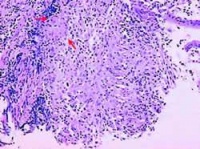

3.组织形态 病理病变附近的淋巴结常有肿大及干酪样坏死。病理组织学检查可见典型的干酪样肉芽肿,常位于黏膜和黏膜下层,很少累及肌层。组织切片抗酸染色可发现抗酸杆菌。

5.胃镜活检 切片抗酸染色阳性,有干酪样肉芽肿。

①干酪样肉芽肿;

②切片抗酸染色或活检材料培养发现结核杆菌;